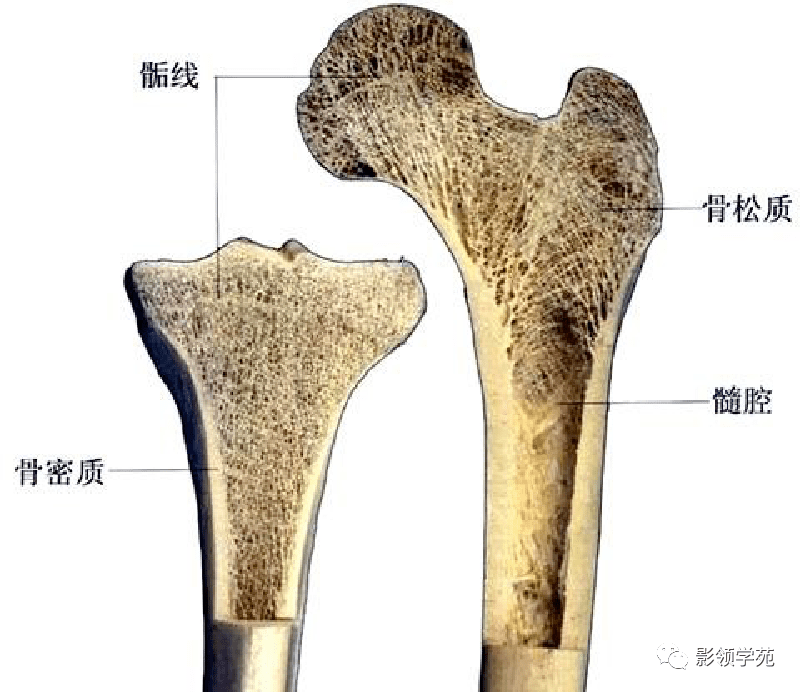

骨骼系统

骨骼系统